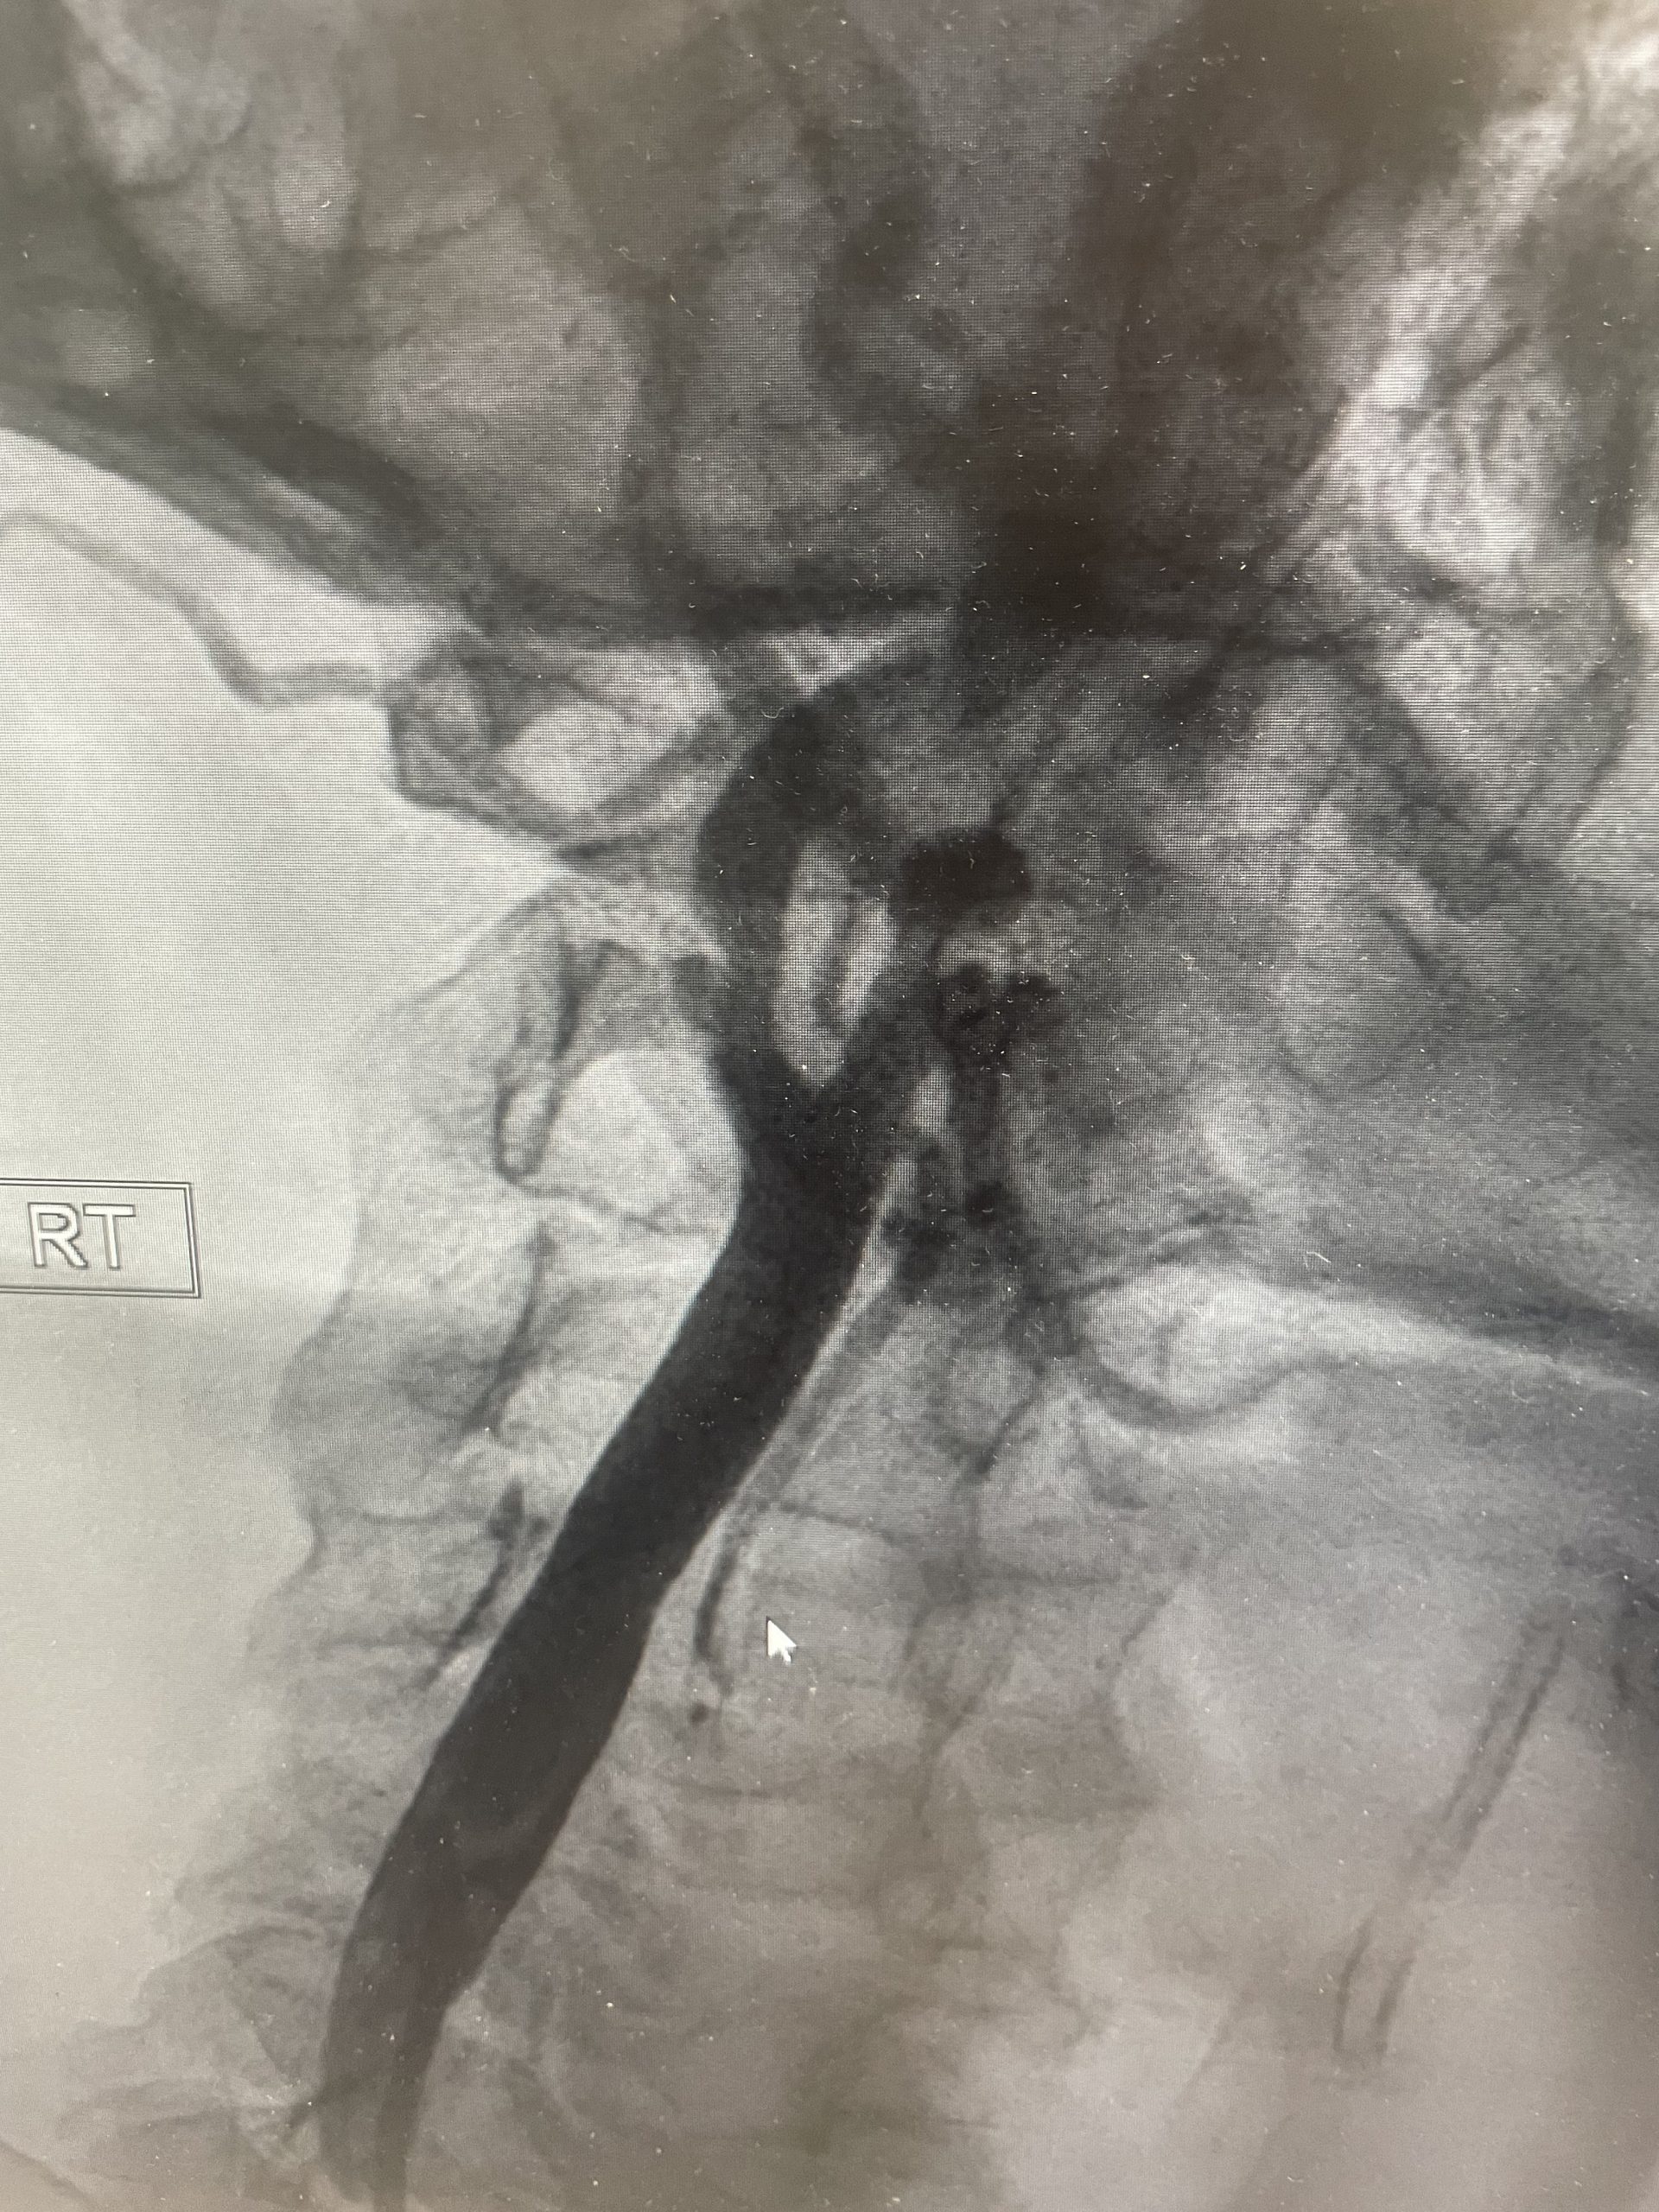

מחקר CREST-2 , מהגדולים והחשובים שבוצעו בתחום מחלות כלי הדם והיצרות עורקי הקרוטיד, פורסם לאחרונה בעיתון הרפואי המוביל NEJM. המחקר מציג תמונה ברורה לגבי הטיפול בחולים שאינם חווים תסמינים מוקדמים (א-סימפטומטיים). התוצאות הראו כי צנתור הקרוטיד עם הנחת סטנט הפחית באופן מובהק את שיעור השבץ לאורך ארבע שנות מעקב. לעומת זאת, בקבוצת הניתוח (אנדארטרקטומיה) לא נמצא יתרון סטטיסטי על פני טיפול רפואי אינטנסיבי בלבד — וגם לא נמצא יתרון על פני סטנט.

בזרוע הסטנט נמצא יתרון ברור: שיעור האירועים היה נמוך משמעותית לעומת טיפול רפואי בלבד (6% לעומת 2.8%, פער של כ־3%). לעומת זאת, בזרוע הניתוח נרשמה ירידה מתונה יותר בשיעור האירועים, שלא הגיעה למובהקות סטטיסטית (5.3% לעומת 3.7%, פער של כ־1.6%).

מחקר ה- CREST-2 מדגיש כי בחולים עם הצרות עורקי הצוואר, קרוטיד, א-סימפטומטית, בעידן של טיפול רפואי מוקפד ואינטנסיבי, נמצא כי צינתור טיפולי עם השתלת תומכן-סטנט הינו בעל יתרון מובהק לעומת טיפול תרופתי בלבד. ניתוח כלי דם, אנדארטרקטומיה אמנם יעיל ובטוח, אך לא הראתה עליונות על פני טיפול שמרני, וגם לא על פני סטנט.